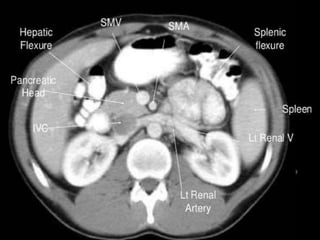

CT cross sectional anatomy.